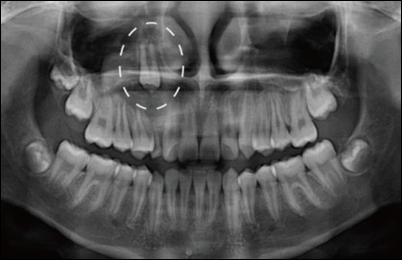

3. 매복

- 일정시기가 지나도 맹출 하지 않고 있는 형태를 말합니다.

3. 외과적 노출

매출 경로를 확보하기 위해서 점막, 골 때로는 치낭 일부까지 제거합니다. 치아는 저항이 가장 적은 방향을 향해 맹출 하는 경향이 있습니다. 입천장 측에 매복된 윗송곳니의 경우에는 외과적 노출술을 시행만으로도 구강 내로 맹출이 유도되기도 합니다.